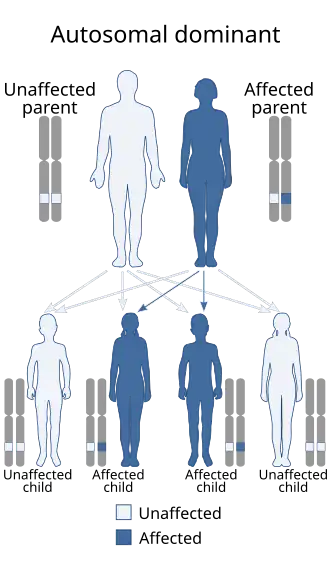

There have been identifiable genetic differences that are better understood. This disease is inherited while following an autosomal dominant pattern.

Inheritance

LENAS is inherited in an autosomal dominant pattern. This means that one copy of the mutated gene in each cell is sufficient to cause the disorder.[2]

If one parent who is unaffected and one parent who is affected with LENAS give birth to four children, at least two of the four will become affected and have the disorder because the affected parent would pass on the one copy of the gene. In most cases, an affected person does inherit the mutation from one affected parent but not all cases.

There have been very few reports of cases that result from new mutations have been seen as well as cases in which there has been no history of LENAS.[2] These few reports are not as concrete or well understood yet and further studies should be conducted.